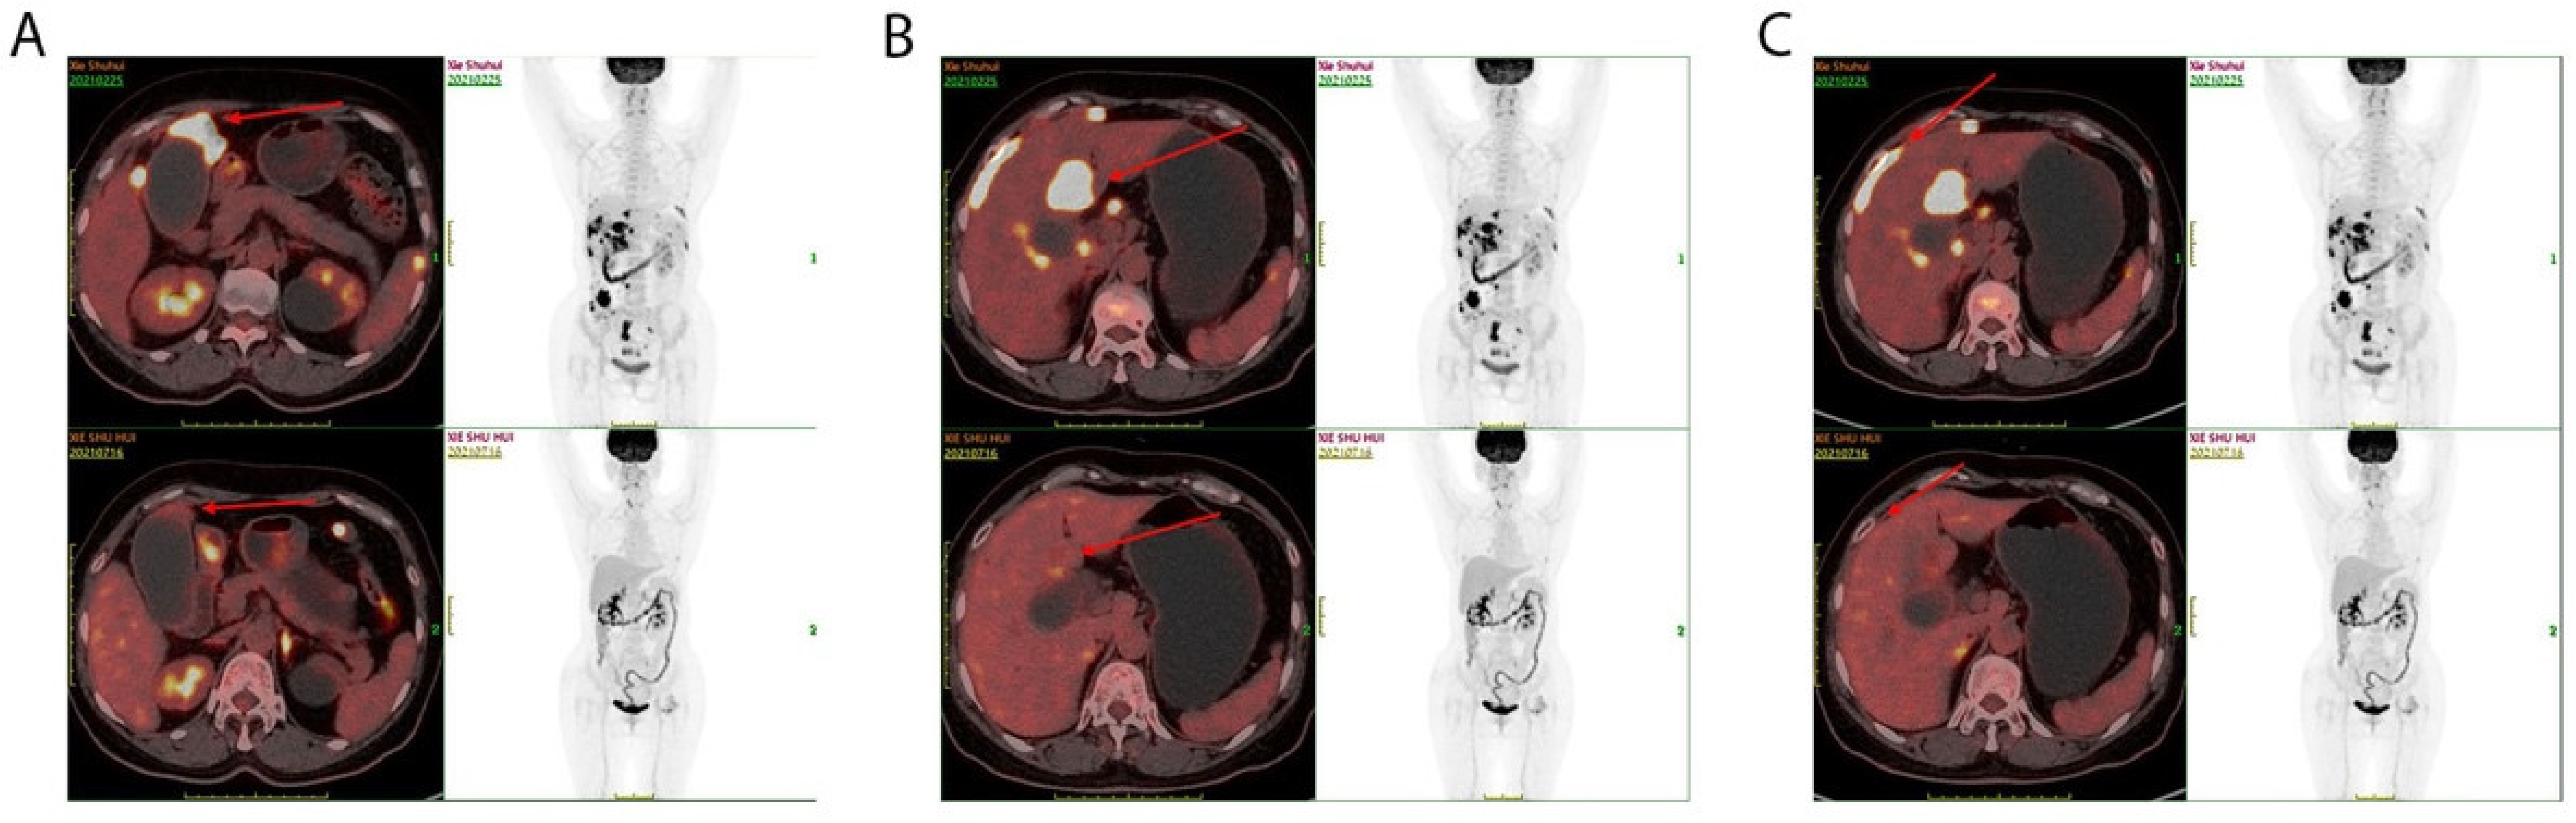

3.2. Clinical Outcome